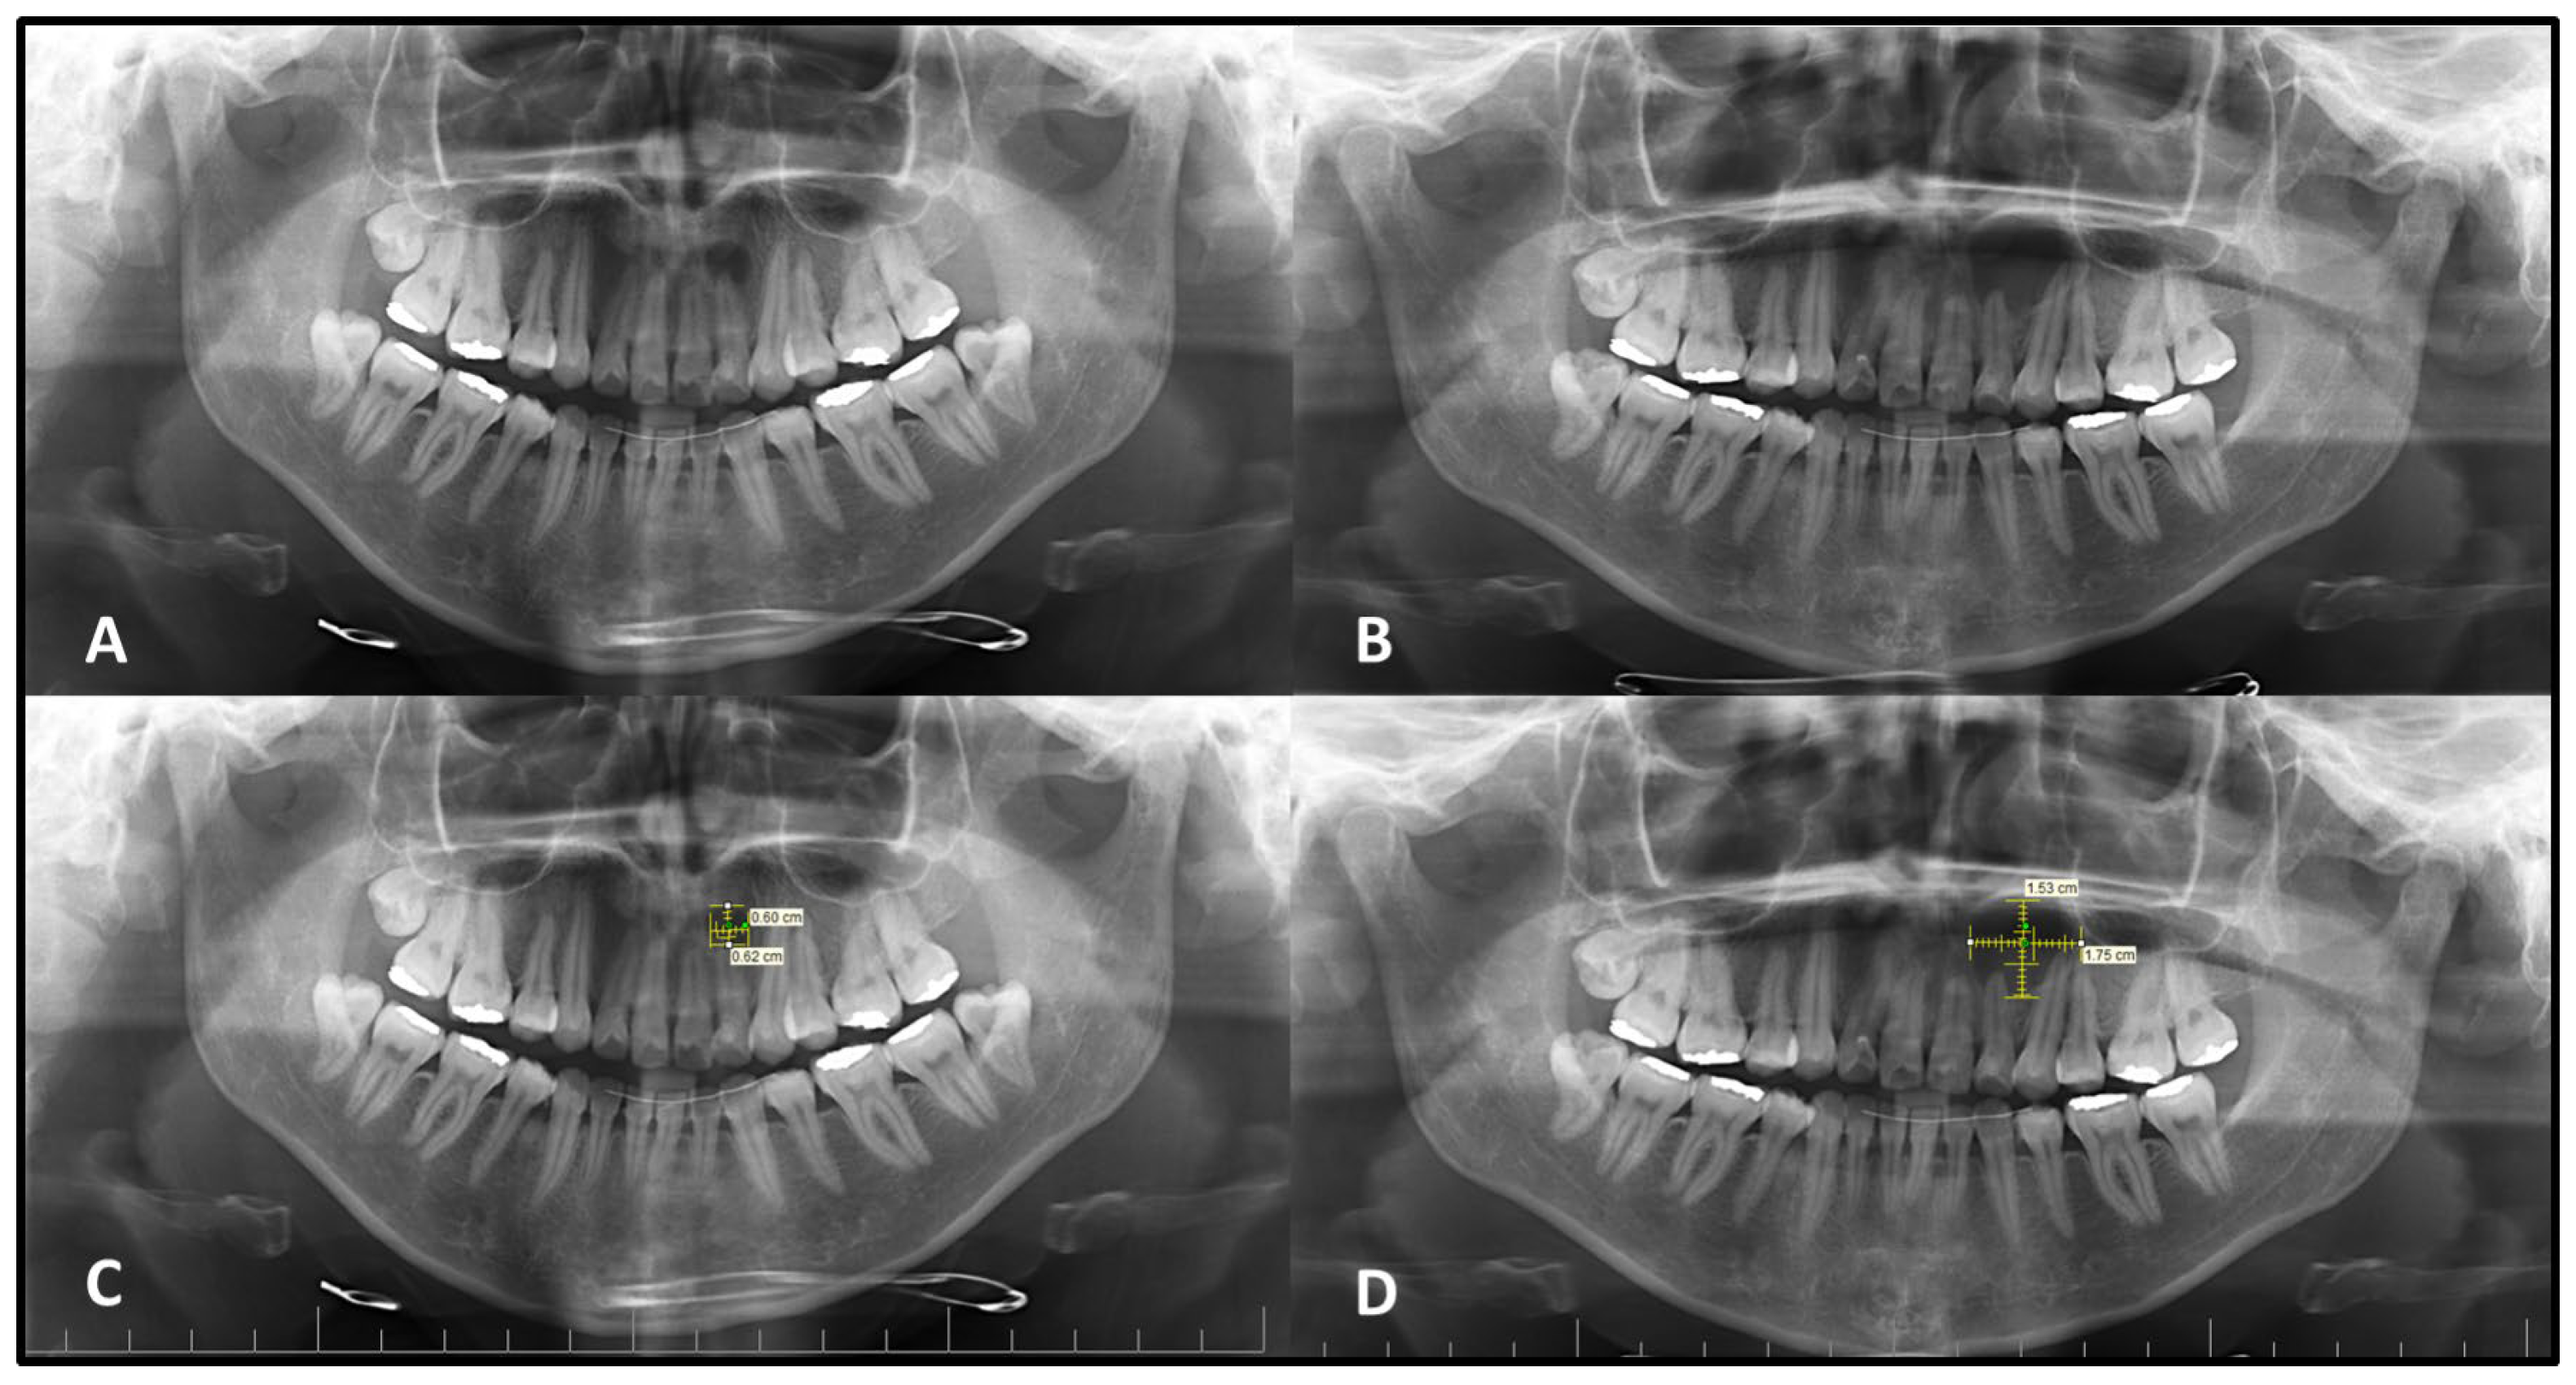

The mean vertical measurement of the intraosseous lesions was found to be 10.9 ± 4.6 mm (Mean ± SD) on the initial PANs (Med: 10.0–IQR: 6.50) and 14.8 ± 5.3 mm (Mean ± SD) on the second PANs (Med: 14.5–IQR: 6.75). A statistically significant increase was observed in vertical dimensions between the two time points (

p < 0.05). For horizontal measurements, the mean values were 12.2 ± 6.5 mm (Mean ± SD) on the initial images (Med: 12.0–IQR: 8.75) and 17.5 ± 8.3 mm on the second PANs (Med: 16.0–IQR: 10.75). This difference was also found to be statistically significant (

p < 0.05), indicating progressive enlargement in both vertical and horizontal dimensions over time (

Figure 1). Because follow-up intervals varied widely (1–13 years), lesions were analyzed in predefined interval groups (1–2 years, 3–4 years, and >5 years) to minimize the effect of heterogeneity on comparability. Lesions with a follow-up interval of 3–5 years demonstrated statistically significantly greater dimensional changes in both horizontal and vertical planes compared to those monitored for 1–2 years or more than 5 years (

p < 0.05) (

Table 1 and

Table 2).

Statistically significant differences were observed in both vertical and horizontal dimensional changes between lesions with corticated and non-corticated borders on the initial PANs (

p < 0.05). Lesions lacking corticated margins demonstrated a greater percentage of growth over time compared to those with corticated boundaries (

Table 3,

Figure 2 and

Figure 3).